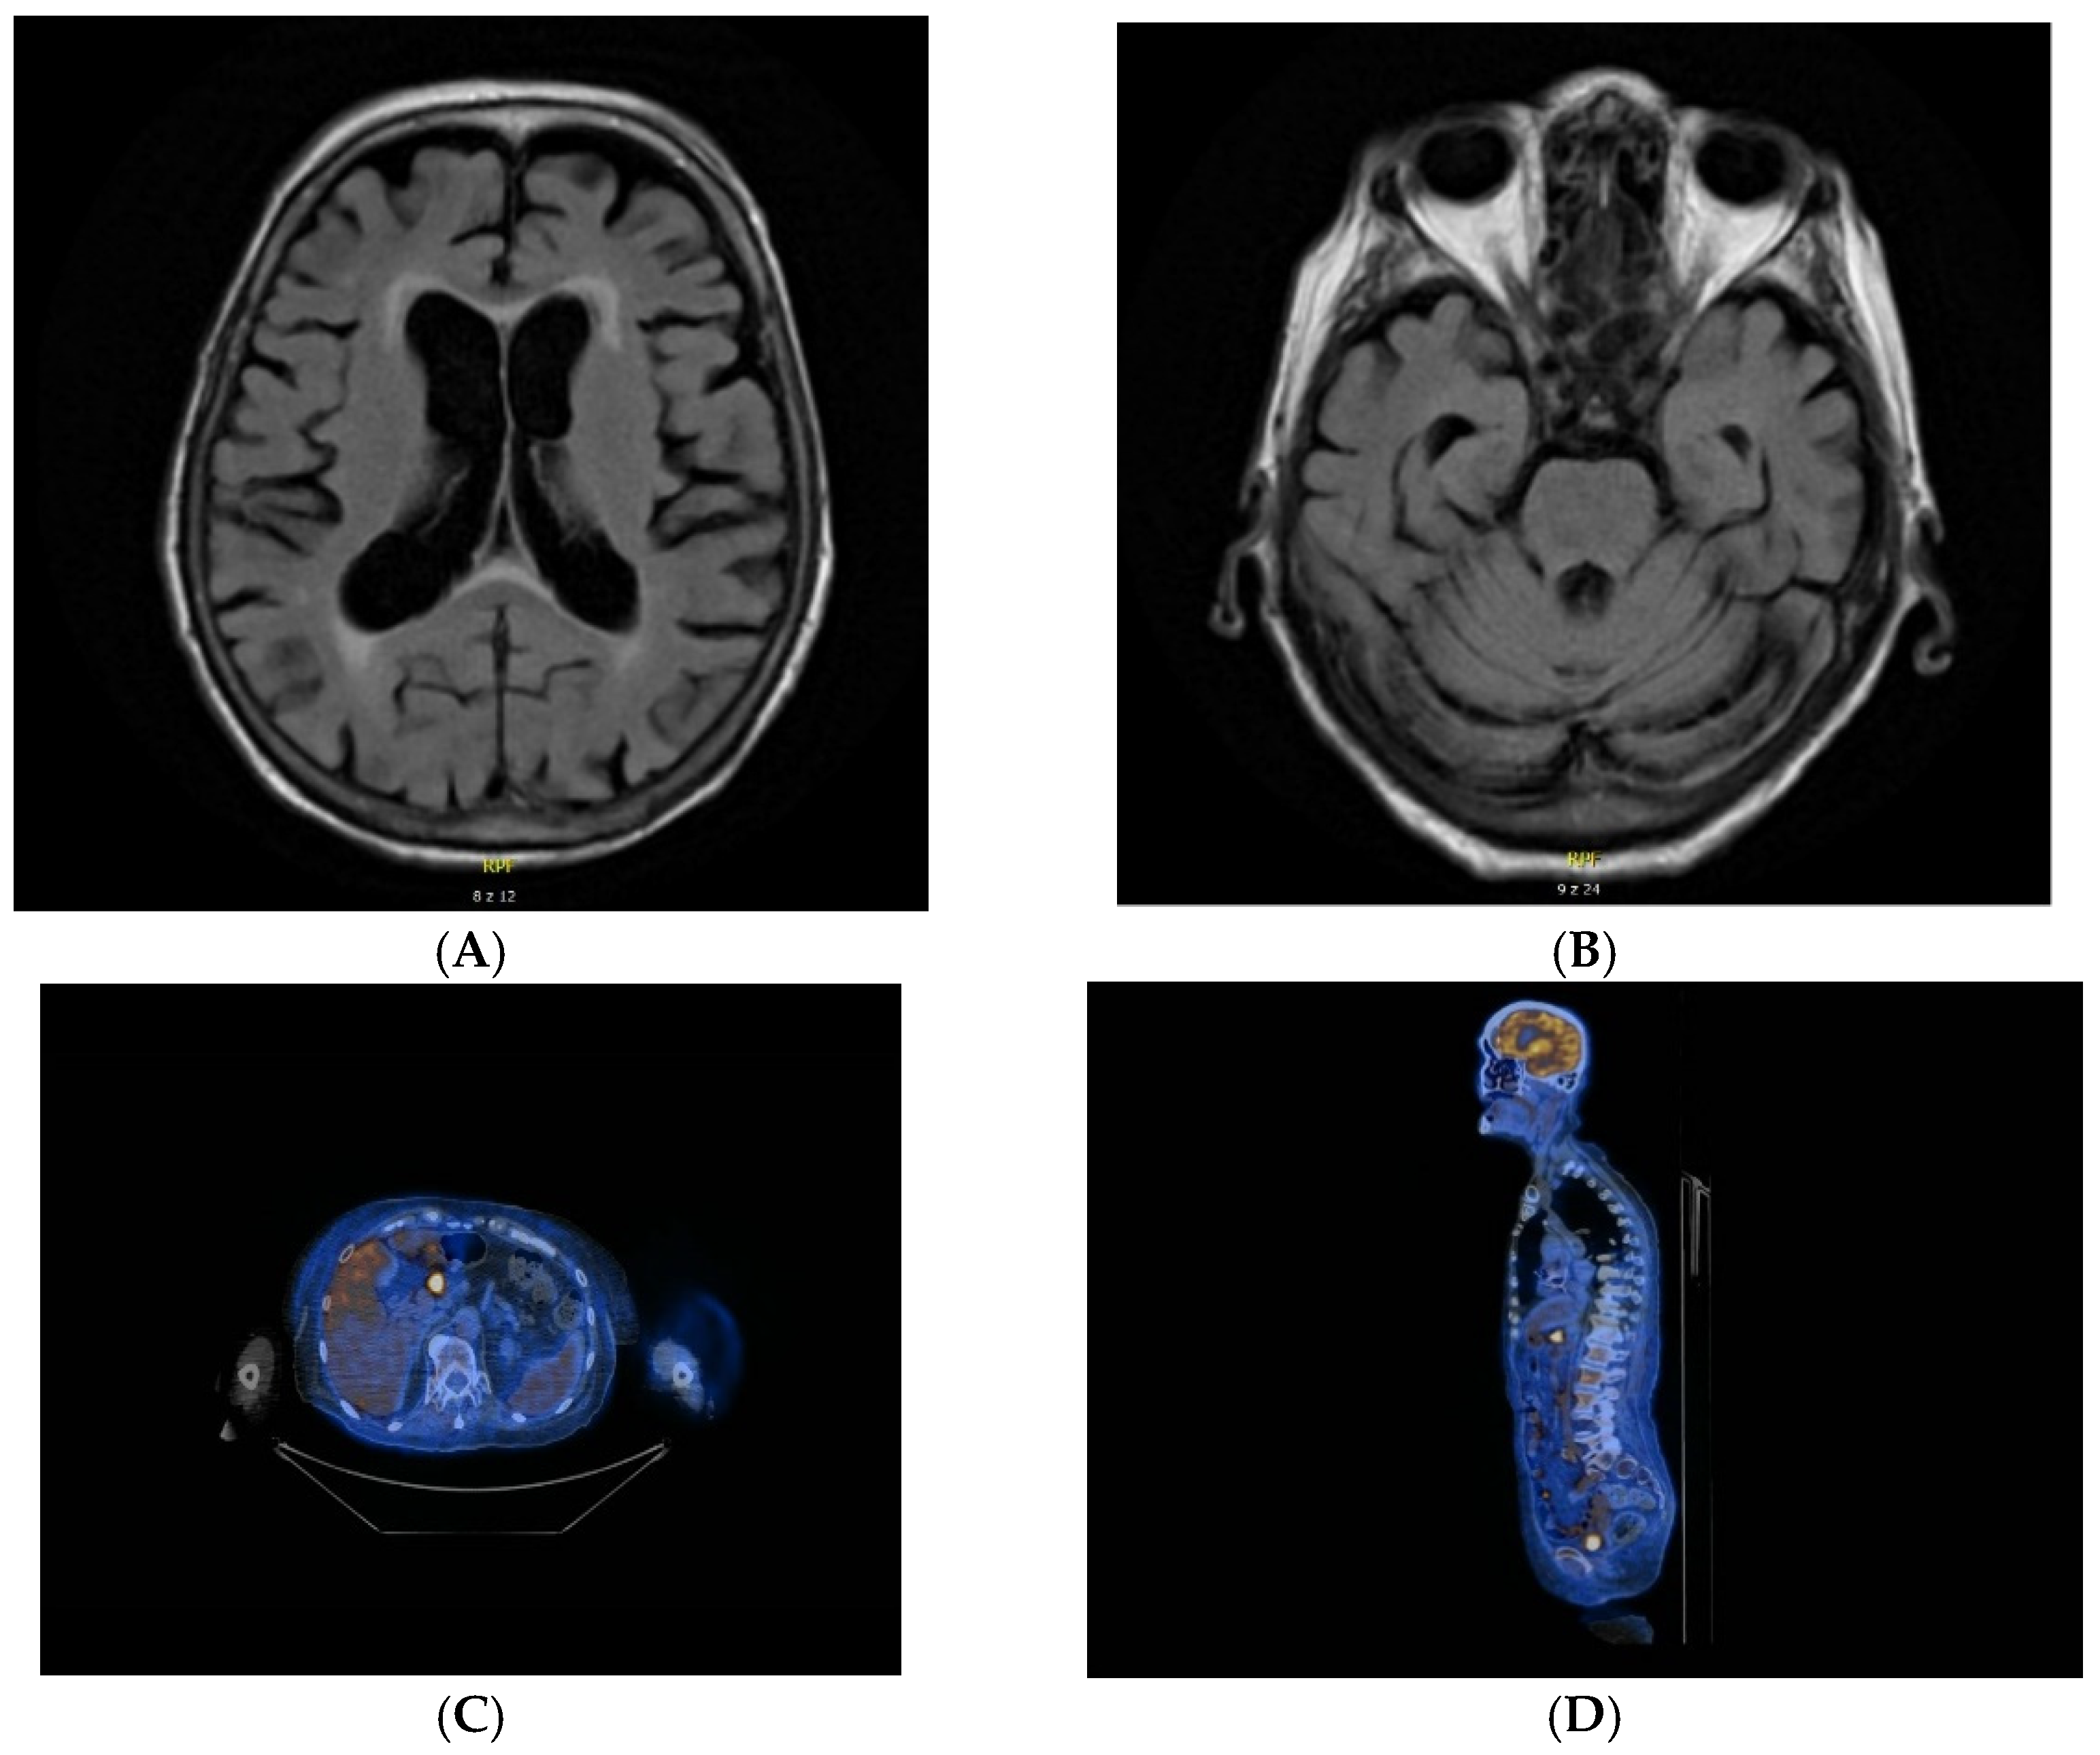

| 4. | F. 32 | Brain MRI: normal | Cytosis 0.018 × 103/uL (0–0.005 × 103/uL) Protein 26.3 mg/dL (20.00–40.00) oligoclonal bands: negative | anti-NMDA | none | increased metabolism of FDG in the topography of numerous lesions in both lungs SUV max up to 7.5 |

| 6. | F. 74 | Brain MRI: epidermal cysts located anteriorly from the medulla oblongata, on the left side; numerous demyelinating lesions located in the white matter of the centrum semiovale, periventricular and paraventricular areas; numerous, small signalless zones on Susceptibility-Weighted Imaging (SWI) which correspond to the presence of haemosiderin deposits—after microchemorrhages | Cytosis 0.002 × 103/uL (0–0.005 × 103/uL) Protein 37.3 mg/dL (20.00–40.00) oligoclonal bands: positive | anti-NMDA | cortical-subcortical atrophy of the brain | not significant |